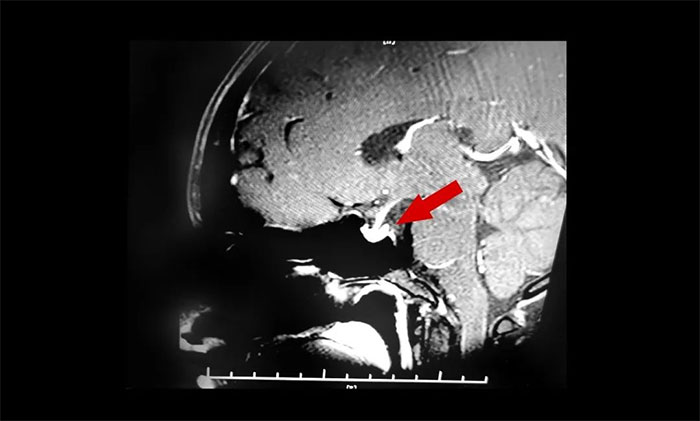

入院时查体,鞍区MRI平扫+增强显示:蝶鞍稍扩大,鞍底骨质下陷;垂体前叶右侧见一矢横高径约1×1×1cm异常信号灶。检查催乳素超3000μIU/mL,远超正常值。

结合患者以往影像资料和内分泌科检查结果,李士其教授、潘仁龙主任会诊后一致达成共识:泌乳素垂体瘤。